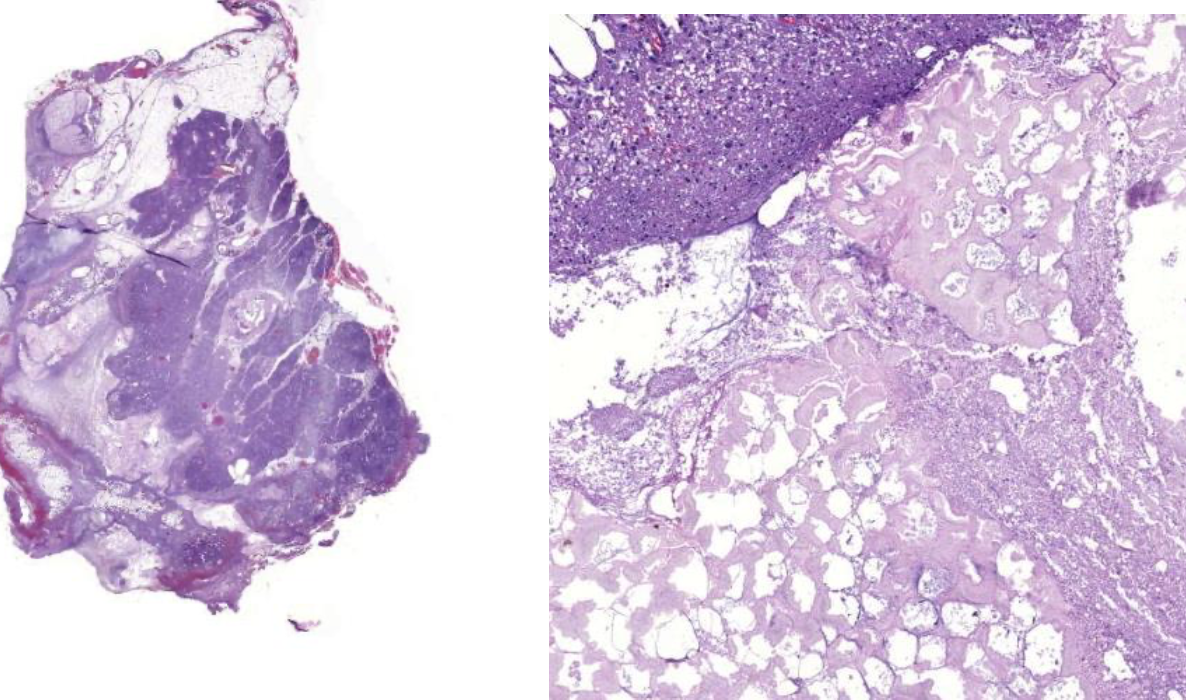

Diagnose?

Squamöse intraepitheliale Läsion (SIL)

Zervikale intraepitheliale Neoplasie (CIN)